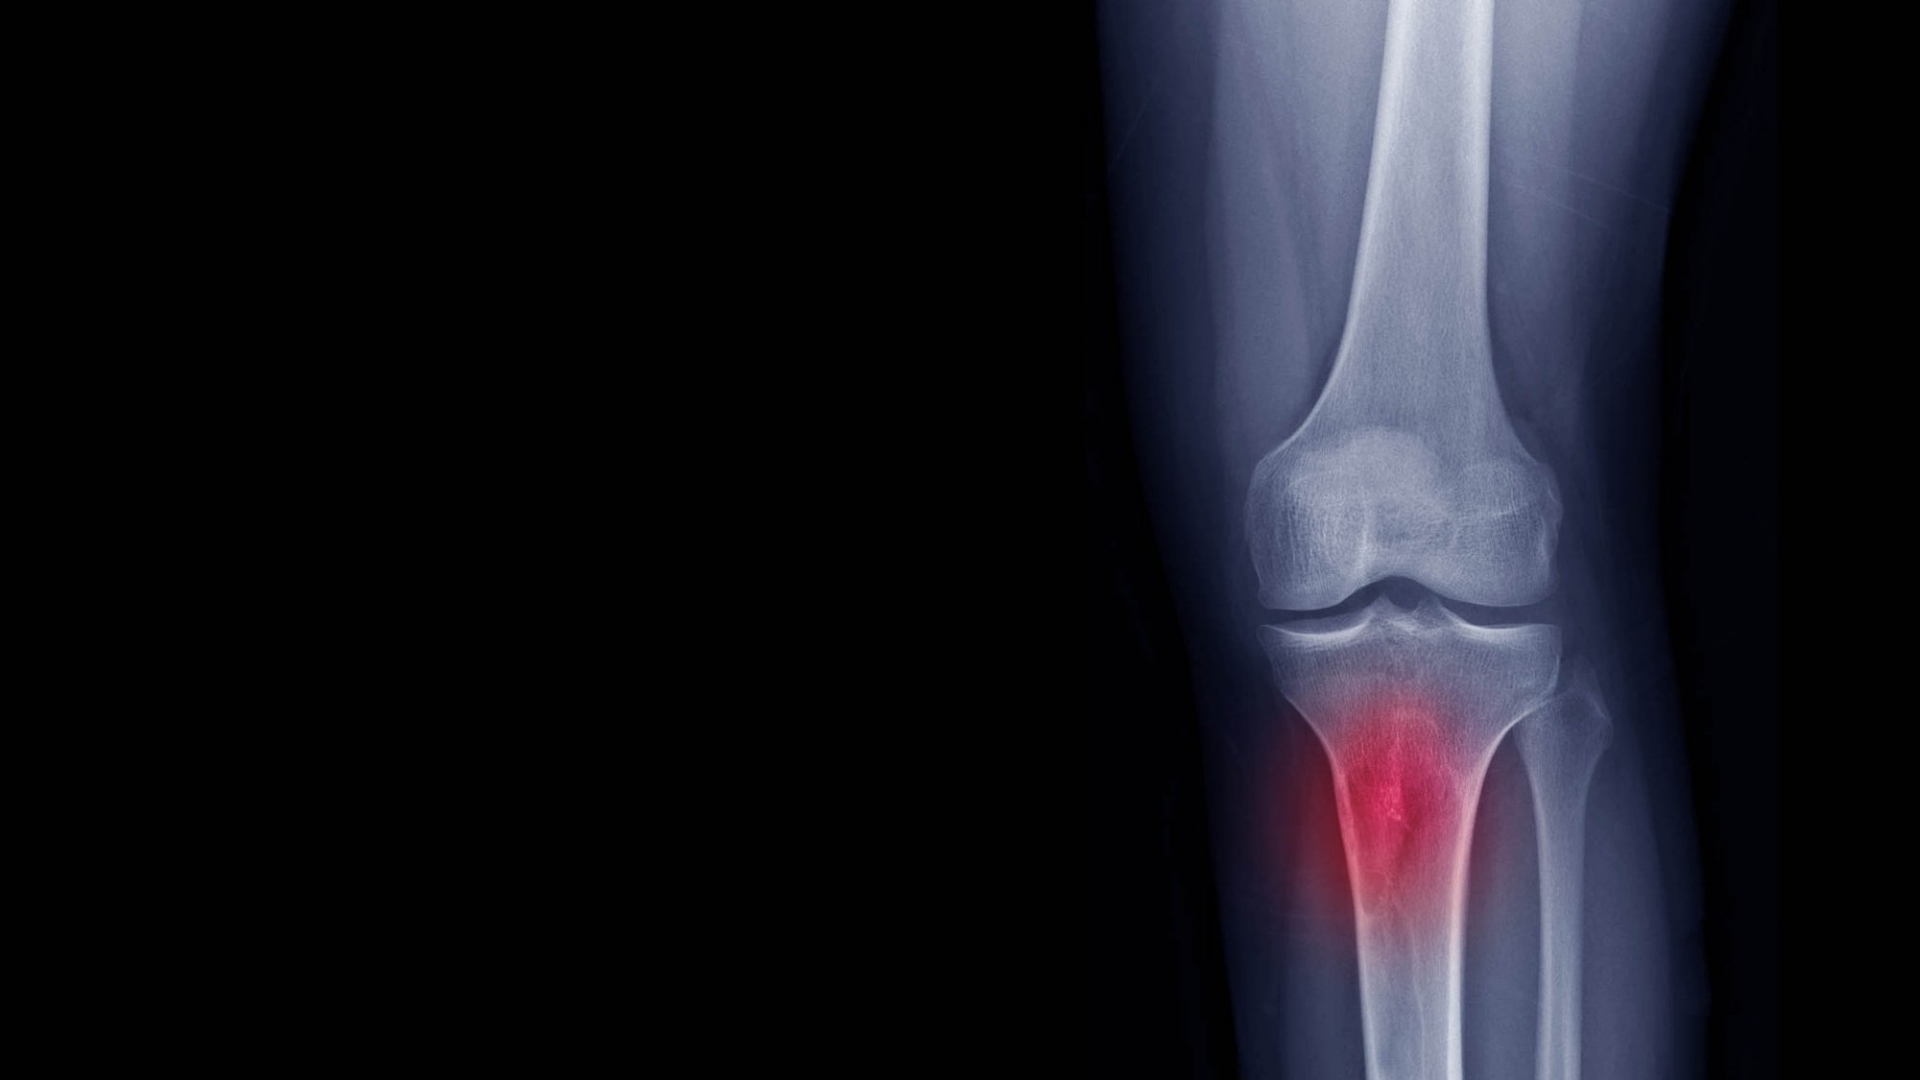

Os tumores podem se espalhar para qualquer lugar do corpo, inclusive para os ossos, configurando a metástase óssea. O local que mais é atingido é a coluna vertebral, mas os ossos do quadril, da perna, dos braços, das costelas e do crânio também podem ser afetados.

Quando o tumor atinge um osso, ela prejudica as células que são responsáveis por mantê-lo saudável e forte. Dessa forma, ele vai ficando cada vez mais frágil e suscetível a fraturas, e isso pode acontecer com pouco ou nenhum trauma. Além disso, no caso de metástase para a coluna, o câncer pode comprimir a medula espinhal, correndo o risco de o paciente sofrer paralisia.